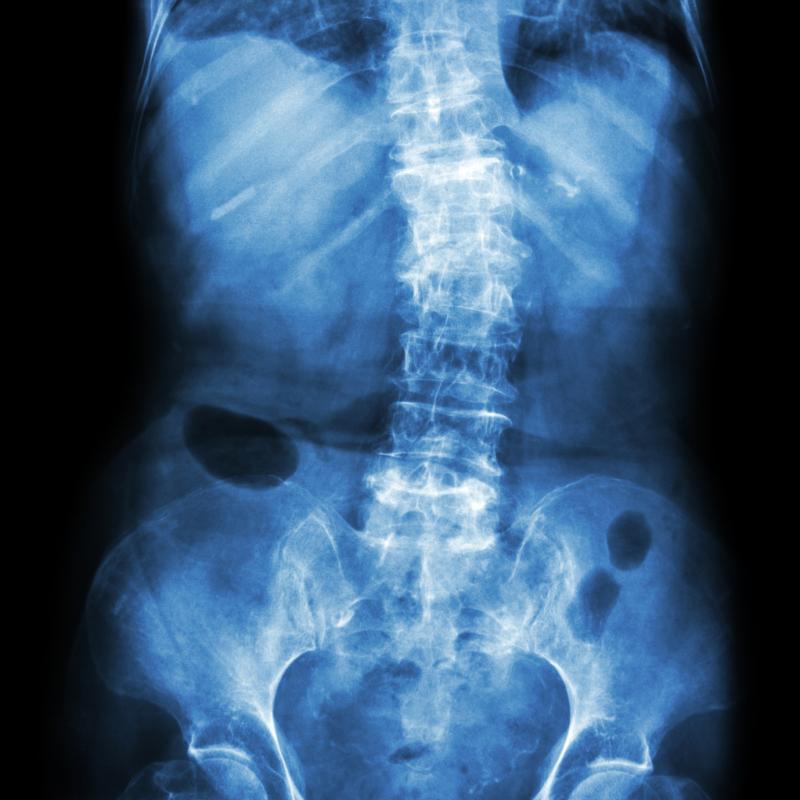

The study included 301 axSpA patients from the German Spondyloarthritis Inception Cohort who had baseline plus at least one sacroiliac radiograph during a 10-year follow-up. The radiographs were scored according to modified New York criteria, while the sacroiliac sum score was calculated as a mean.

Of the patients, 166 had nonradiographic (nr-axSpA) and 135 had radiographic (r-axSpA) disease. The overall population contributed 737 radiographic intervals.